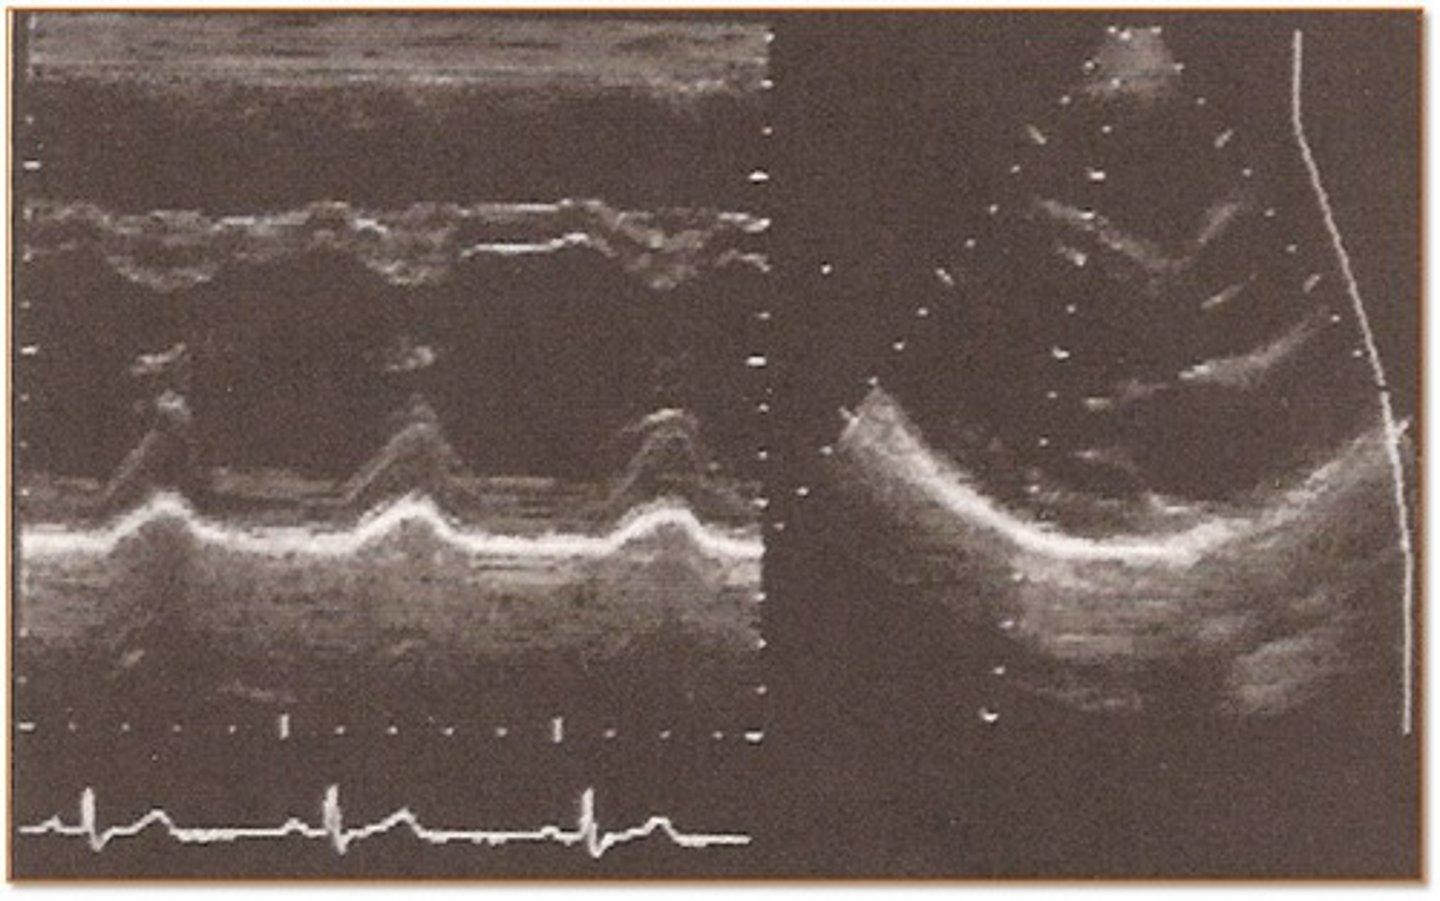

Referencing the image to the right, which imaging mode is illustrated and what function is demonstrated?

Doppler mode illustrating blood flow through the heart

Spectral Doppler mode illustrating flow velocities

Gray scale mode illustrating heart valve motion

M-mode illustrating heart wall motion and heart valve motion